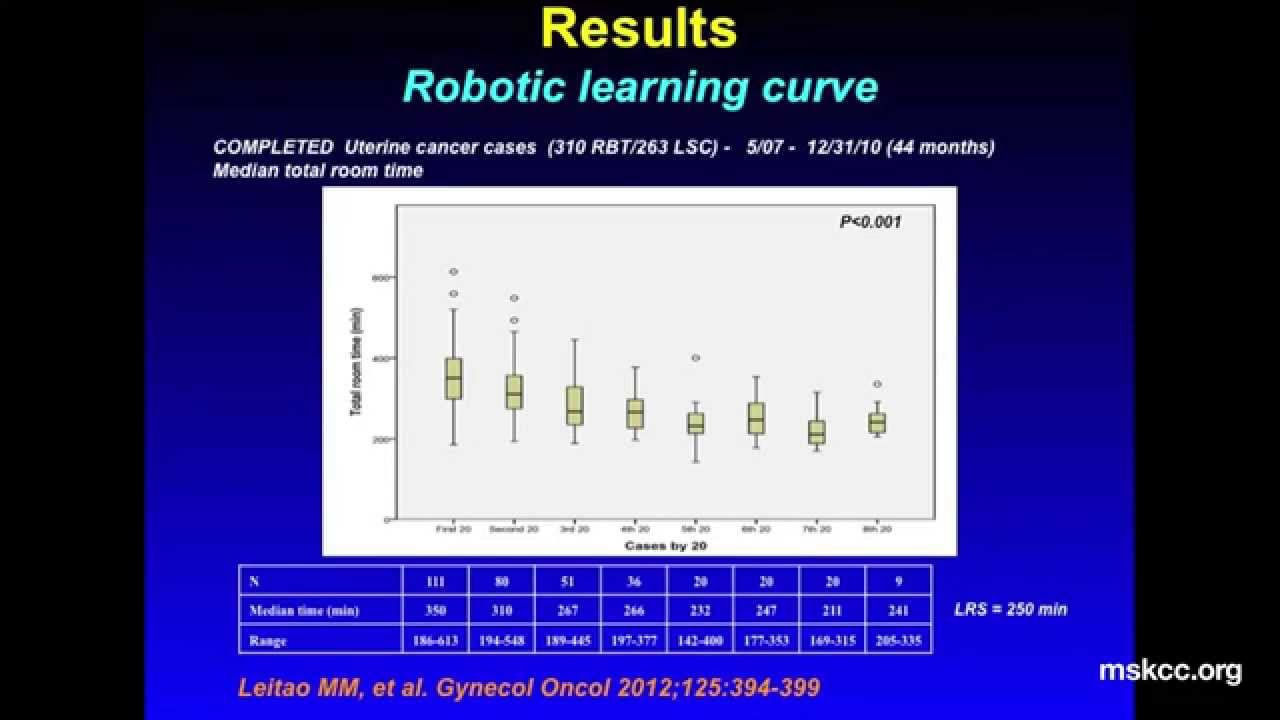

A Detailed Analysis of Learning Curve

Learning Curve in Robotic Surgery